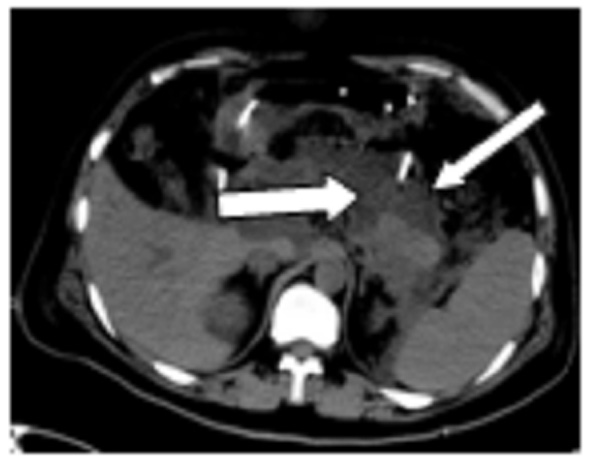

图 1 图中箭头提示胰周积液

图 3 粗箭头提示胰尾积液基本吸收,细箭头为穿刺管位置